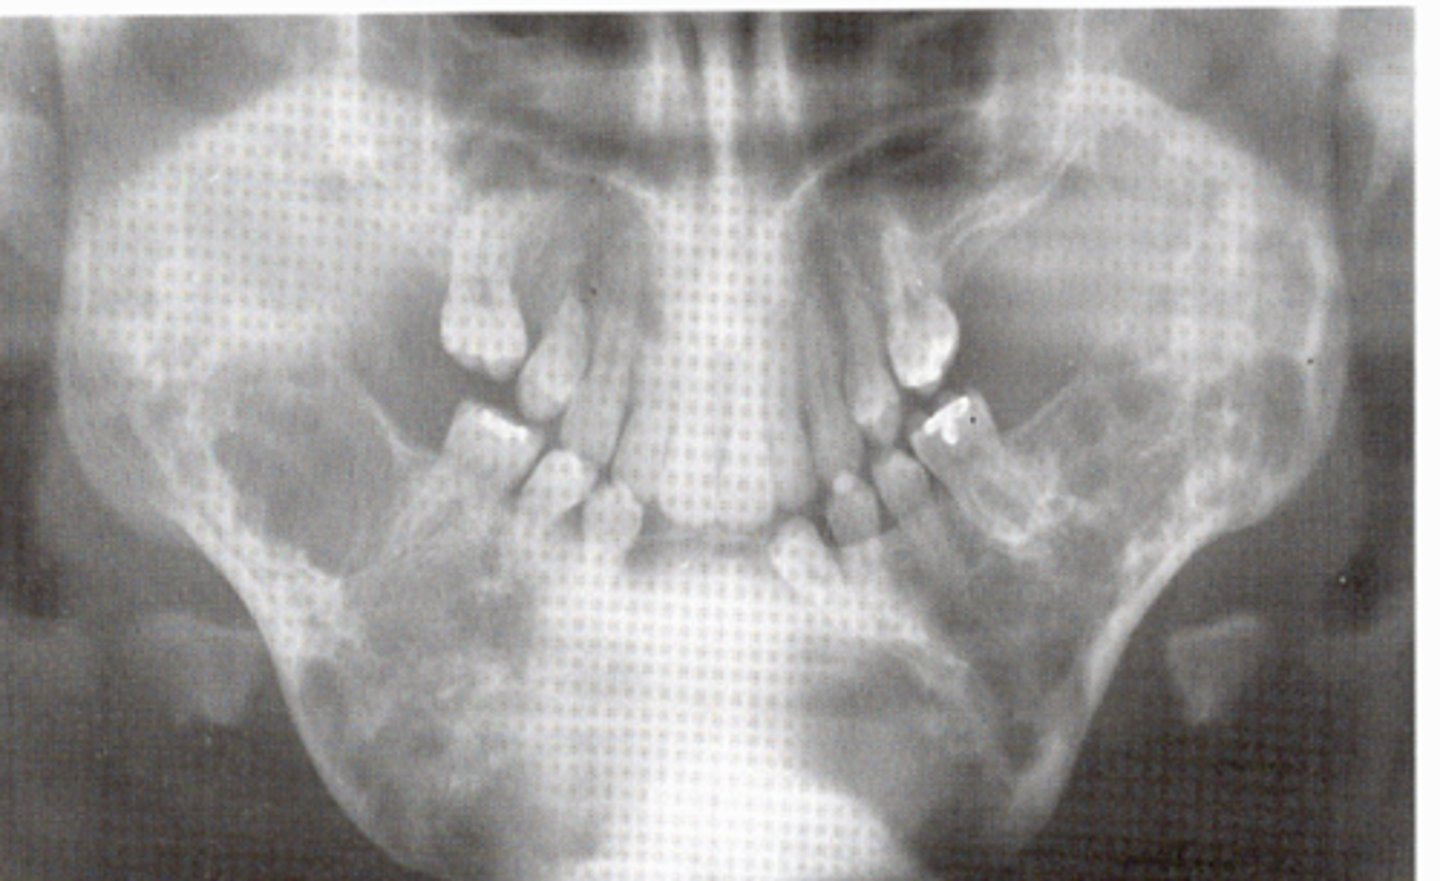

what is cherubism

it is a rare genetic disorder named for the appearance of plump cheeks

cherubism

cause: inherited autosomal dominant

clinical features: plump cheeks; upturned eyes; histologically GIANT CELL LESIONS

oral features: posterior mndible; usually symmetric

radiographic: bilateral multiocular lucencies

population: children